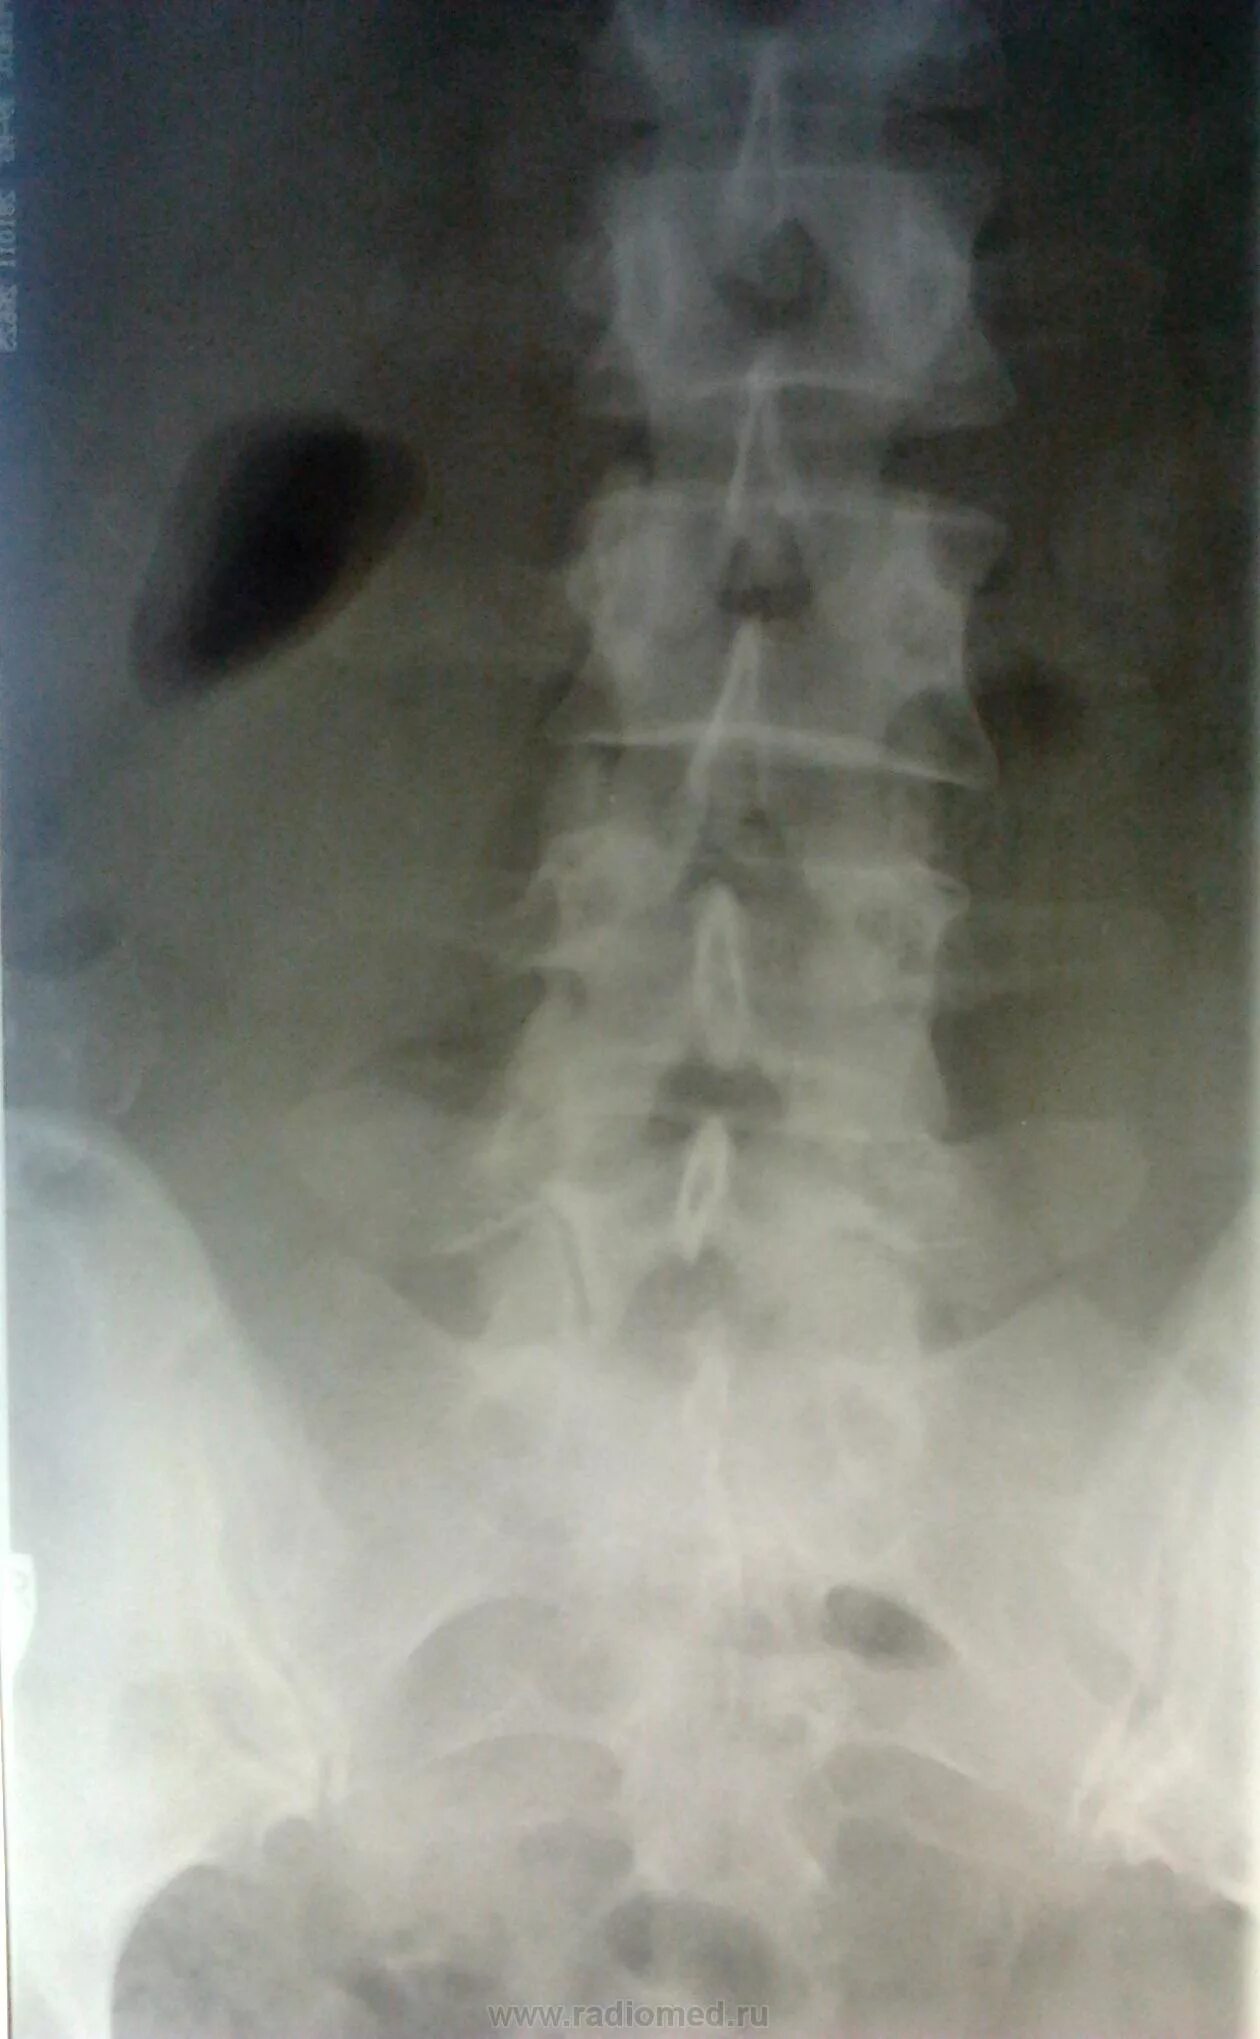

Снимок копчика